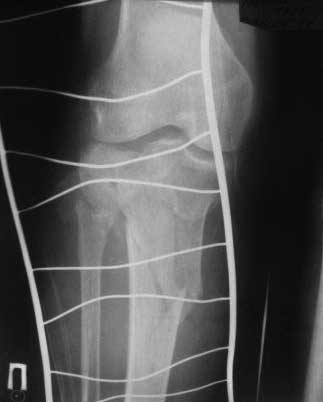

Уважаемые колллеги! Женщина 73 года, травма в результате падения с высоты своего роста, получила закрытый оскольчатый внутрисуставной перелом проксимального отдела большеберцовой кости. Сельский житель, ничем до травмы особо не болела, аткивная. Единственная жалоба на появление гематом и ран даже при незначительных ушибах. Рентгеновские снимки прилагаю, если есть необходимость, позже выложу КТ. А вот кожа... пальпаторно очень тонкая, практически пергамент, сухая, тургор снижен (есть фото). Прошу вашей помощи. Учитывая состояние мягких тканей, оскольчатый перелом большеберцовой кости на большом протяжении, есть вопросы: -чем фиксировать; - как (MIPO?) и в какой последовательности; -когда начинать операцию? Заранее благодарен

Перелом нестабильный, двухмыщелковый (Schatzker VI). Учитывая возраст больной и состояние мягких тканей (судя по фотографии, выраженные расстройства микроциркуляции), первым этапом стабилизируйте перелом (скелетное вытяжение за бугор пяточной кости), в течение дней 10 - инфузионная вазотропная терапия (трентал, но-шпа, клексан).

2. В аппарате для уточнения анатомии повреждения (костного) нужно выполнить КТ (лучше в аппарате, а не до него). Там скорее всего увидим не только импрессию наружного мыщелка, но и перелом внутреннего со смещением.

Следовательно начинать фиксацию надо с внутреннего мыщелка и не снимая аппарата(доступ 1 задне-медиальный, ORIF, DCP 3.5 мм, LC-DCP 3.5 мм, но лучше LCP 3.5 мм), затем восстанавливать наружный мыщелок (доступ 2 - наружный парапателлярный с прямым контролем репозиции суставной поверхности, ORIF суставного компонента, LCP-PLT 5.0 мм). На втором доступе действительно можно немного сэкономить - протолкнуть пластину над костью и зафиксировать дистально из отдельного минидоступа или проколов.

На боковом рентгене, явный задний смещенный компонент. КТ поможет увидеть "вершину" перелома, куда надо поставить антискользящую пластину из заднего или задне-медиальнего доступа. Для стабилизации боковой колонны традиционный боковой доступ через Girdle tubercle с длинной блокирующей пластиной. Одна задняя подпорка не удержит медиальную колонну, требуется длинная медиальная пластина.